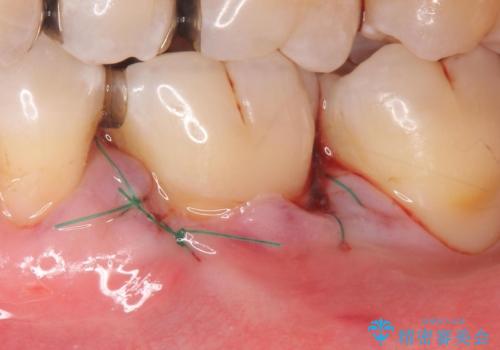

- 奥歯の歯茎が下がっていて(歯肉退縮)歯が染みるとのことで来院された患者様です。

退縮した歯茎に対して移植をすることで、しみる場所を覆う計画です。

歯根の分岐部よりも根尖側の頬側面が露出している状態でしたが、露出部位を分岐部までに抑えることができました。